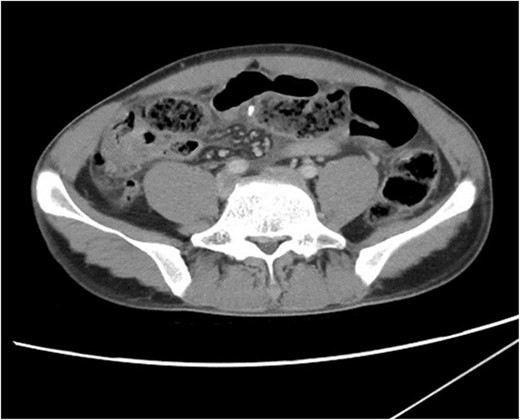

On initial presentation the patient was pyrexial, with a fever of 38.9 °C, but haemodynamically stable. Abdominal examination revealed diffuse peritonitis. Laboratory results showed a mild lecuocytosis (white cell count 10.5 g/L) but were otherwise within normal limits. Plain film X-ray of his abdomen was suggestive of pneumoperitoneum (see Fig. 1). A clinical diagnosis of suspected perforated duodenal ulcer was made and the patient was initially resuscitated with intravenous fluids and broad-spectrum antibiotics while a computed tomography (CT) scan of his abdomen and pelvis was arranged. The CT revealed showed a small rod-shaped radiopaque object in a thickened small bowel loop in the hypogastric region, with associated free abdominal fluid and air (see Fig. 2). This was concerning for small bowel perforation due to a foreign body.

CT scan of abdomen and pelvis. A radiopaque object is seen extruding from a thickened small bowel loop with associated free peritoneal fluid, concerning for foreign body perforation of small bowel.